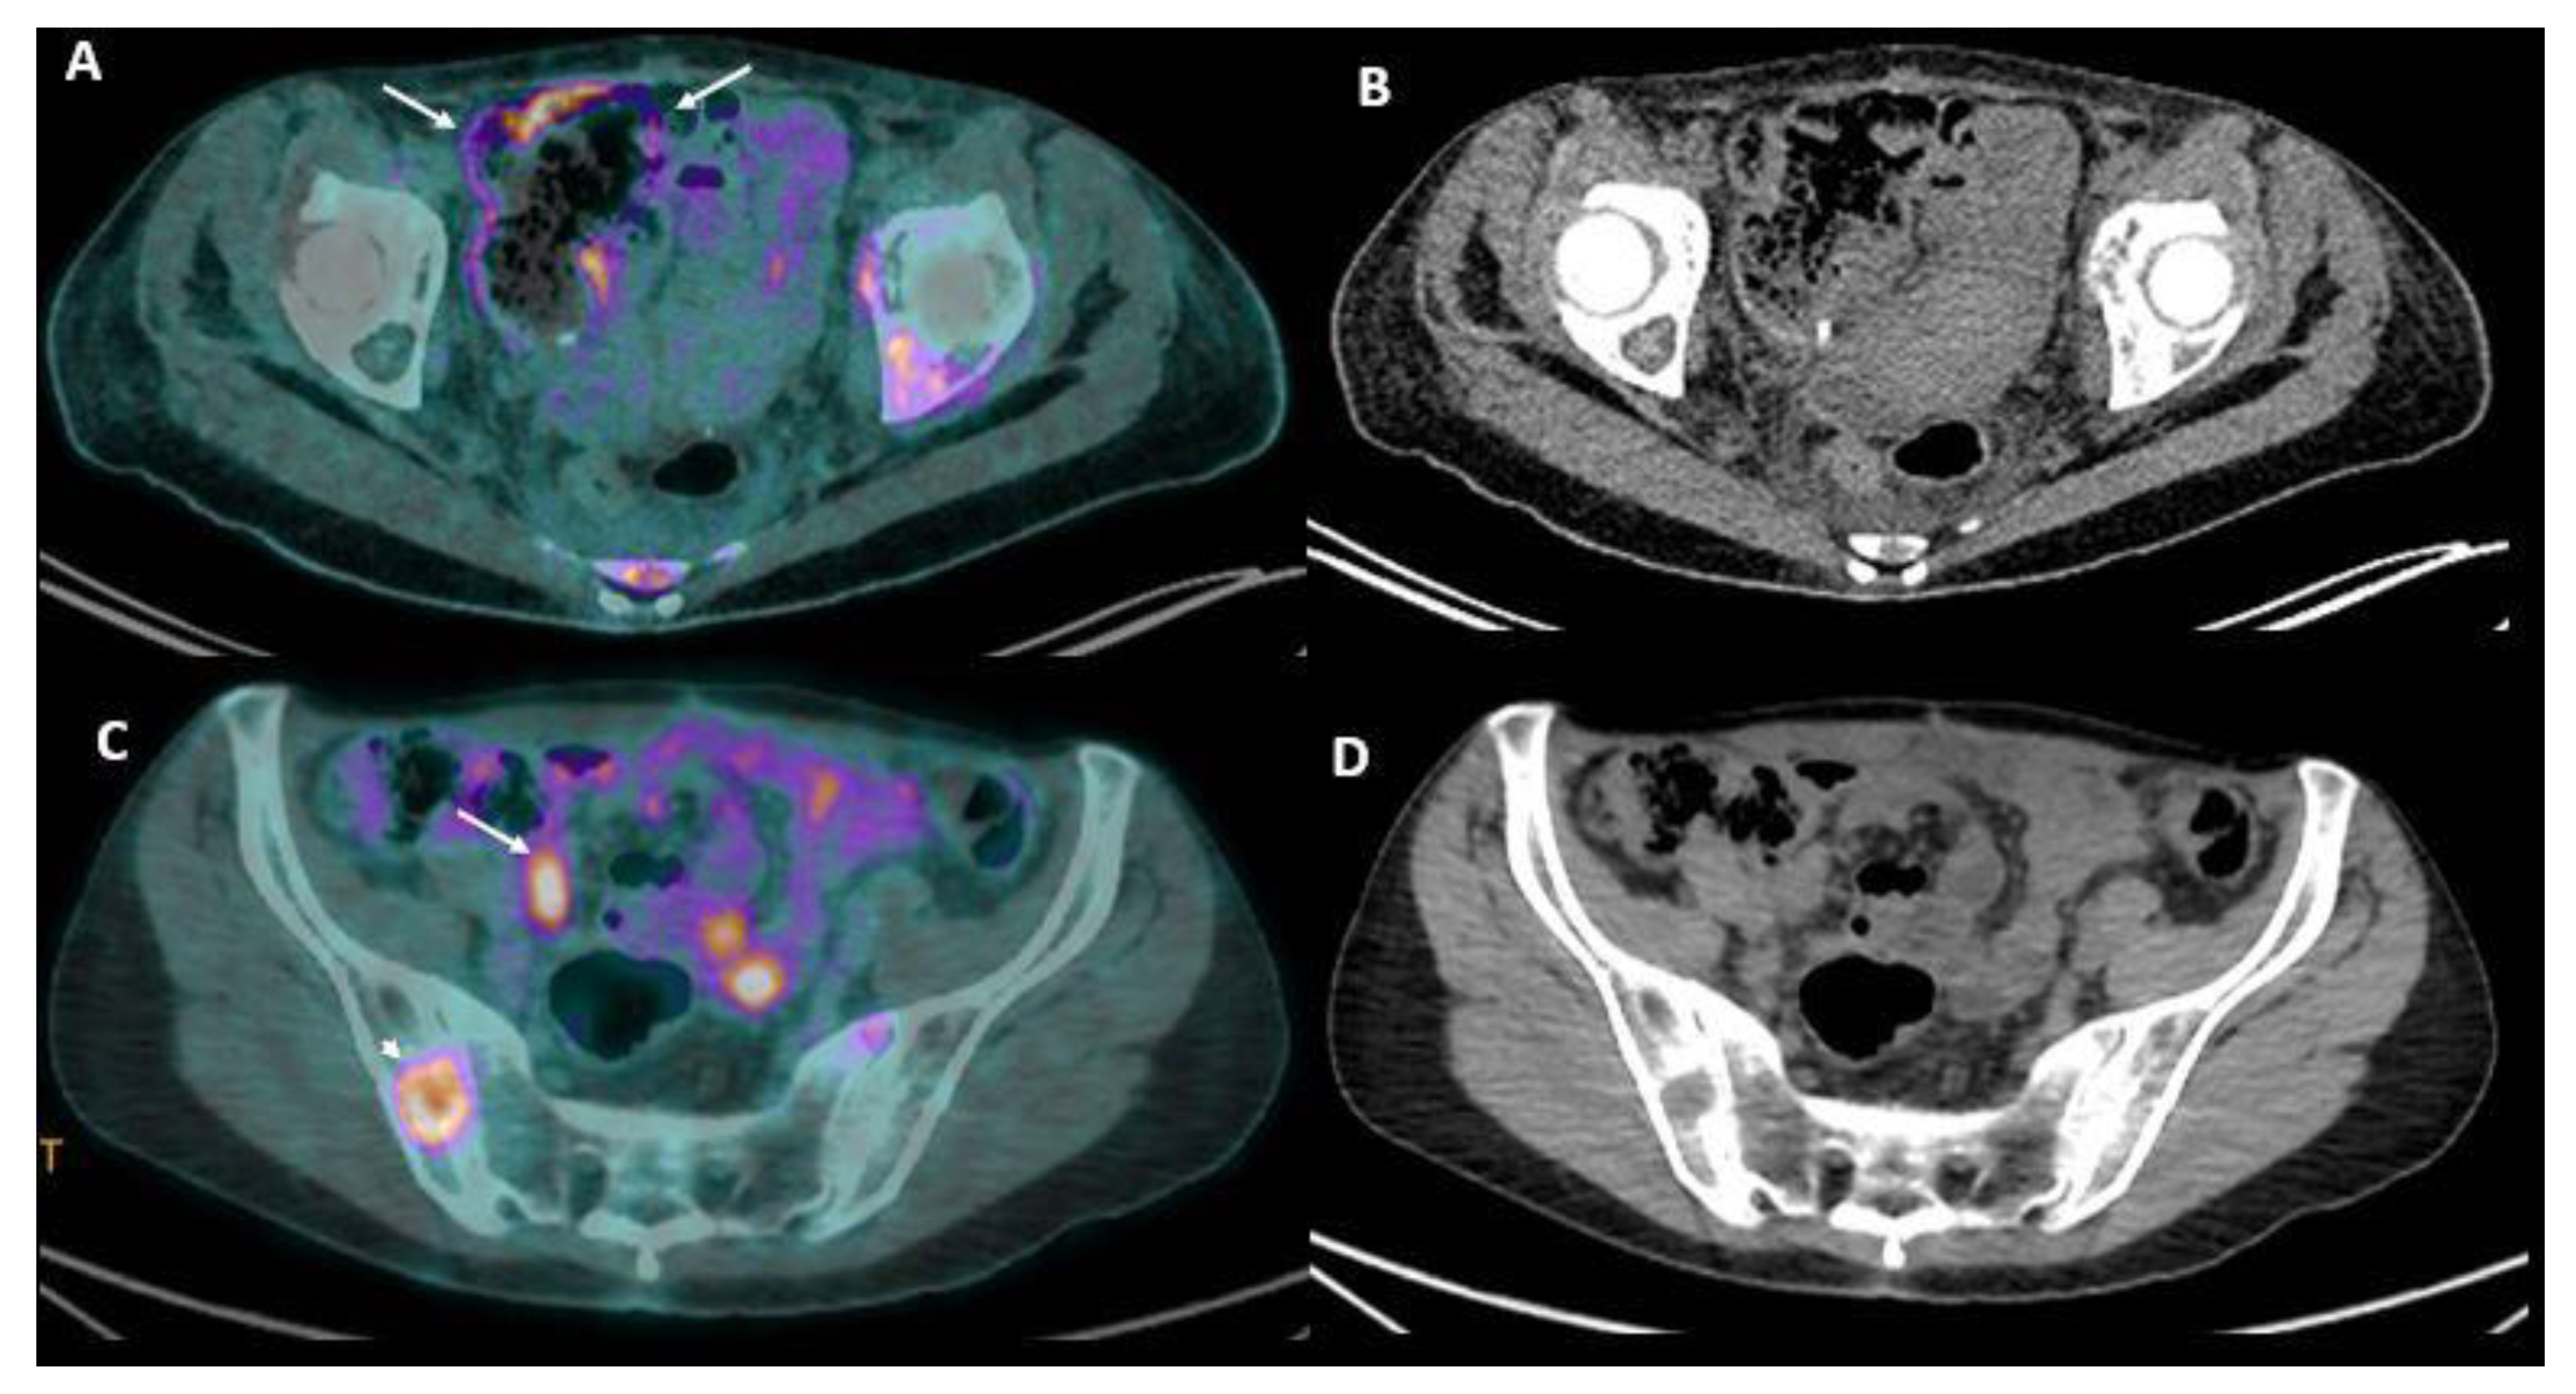

- Lim, J.S.; Kim, M.-J.; Yun, M.J.; Oh, Y.T.; Kim, J.H.; Hwang, H.S.; Park, M.-S.; Cha, S.-W.; Lee, J.D.; Noh, S.H.; et al. Comparison of CT and 18F-FDG PET for detecting peritoneal metastasis on the preoperative evaluation for gastric carcinoma. Korean J. Radiol. 2006, 7, 249–256. [Google Scholar] [CrossRef] [PubMed] [Green Version]

- Panagiotidis, E.; Datseris, I.E.; Exarhos, D.; Skilakaki, M.; Skoura, E.; Bamias, A. High incidence of peritoneal implants in recurrence of intra-abdominal cancer revealed by 18F-FDG PET/CT in patients with increased tumor markers and negative findings on conventional imaging. Nucl. Med. Commun. 2012, 33, 431–438. [Google Scholar] [CrossRef] [PubMed]

- Tawakol, A.; Abdelhafez, Y.; Osama, A.; Hamada, E.; El Refaei, S. Diagnostic performance of 18F-FDG PET/contrast-enhanced CT versus contrast-enhanced CT alone for post-treatment detection of ovarian malignancy. Nucl. Med. Commun. 2016, 37, 453–460. [Google Scholar] [CrossRef] [PubMed]

- Sommariva, A.; Evangelista, L.; Pintacuda, G.; Cervino, A.R.; Ramondo, G.; Rossi, C.R. Diagnostic value of contrast-enhanced CT combined with 18-FDG PET in patients selected for cytoreductive surgery and hyperthermic intraperitoneal chemotherapy (HIPEC). Abdom. Radiol. 2017, 43, 1094–1100. [Google Scholar] [CrossRef] [PubMed]

- Dromain, C.; Leboulleux, S.; Auperin, A.; Goere, D.; Malka, D.; Lumbroso, J.; Schumberger, M.; Sigal, R.; Elias, D. Staging of peritoneal carcinomatosis: Enhanced CT vs. PET/CT. Abdom. Imaging 2008, 33, 87–93. [Google Scholar] [CrossRef] [PubMed]